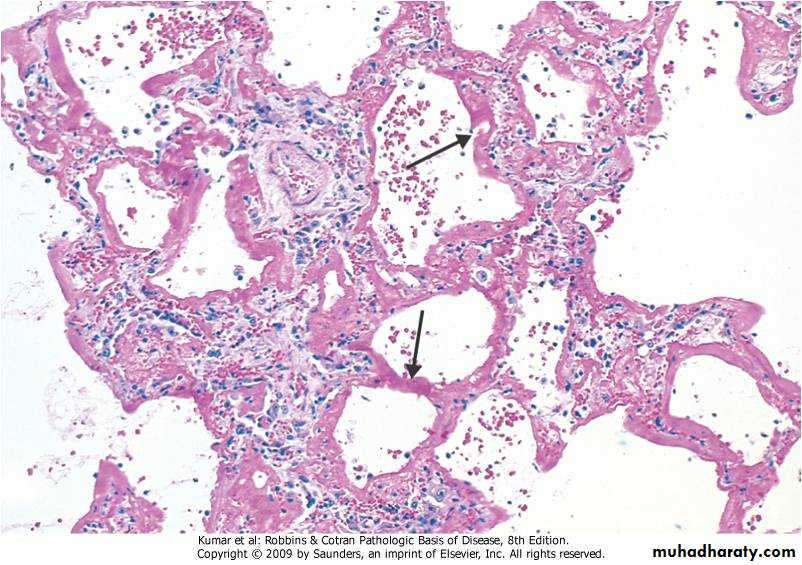

A clinical syndrome caused by diffuse alveolar capillary endothelial and epithelial cell damage.Increased permeability result in exudation of fluid.

Clinically: severe respiratory distress , cyanosis & respiratory failure.

Grossly:

The lung is heavy red congested &edematous

Micro:

Diffuse alveolar wall damage( epithelial & endothelial)

Alveolar wall is lined by hyaline materials Latter on intra alveolar organization takes place